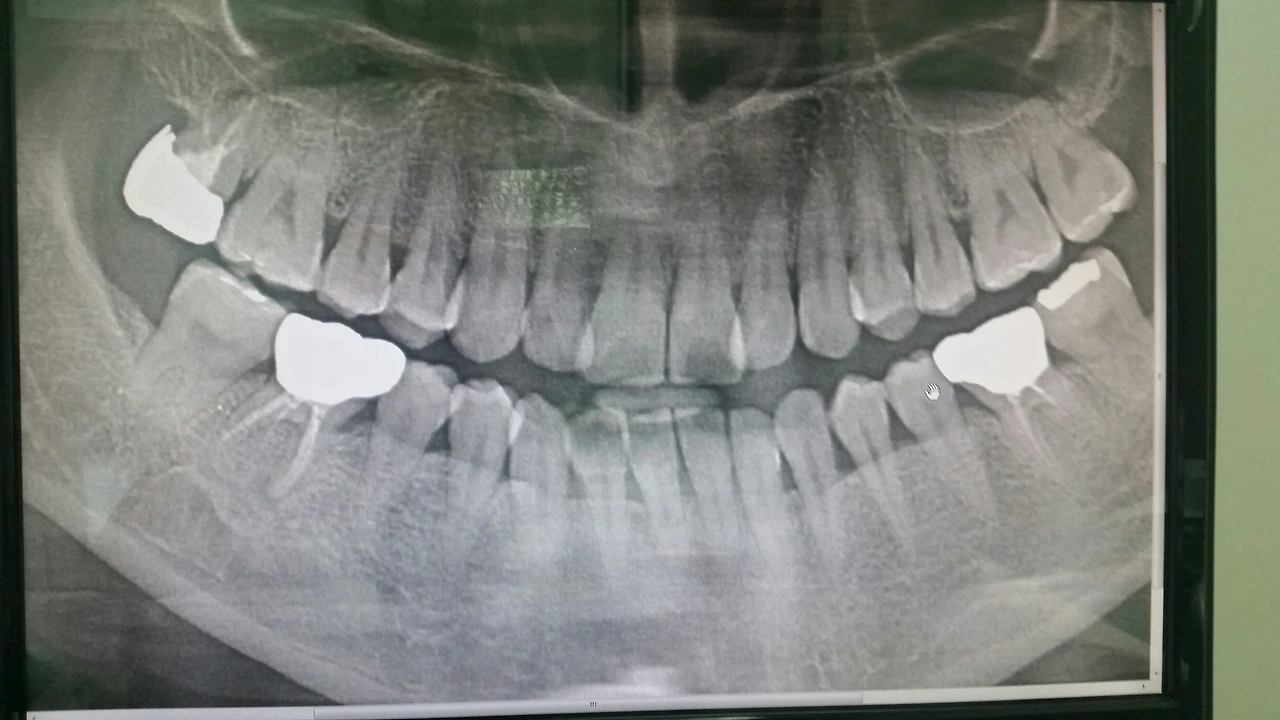

치통으로 최근 치과 방문 찍은 x ray

치통으로 방문한 이번 치료는 2달이란 시간이 걸렸다.

지르코니아 도자기 크라운으로 치통이 있던 어금니와 전에 했던 골드크라운에 구멍이 생겨 바꿔야 했다.